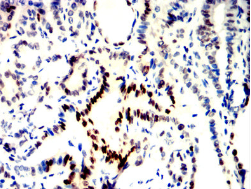

NPM2 Mouse Monoclonal antibody[2B431]

NPM2 (Nucleophosmin/Nucleoplasmin 2) is a Protein Coding gene. Gene Ontology (GO) annotations related to this gene include nucleic acid binding and enzyme binding. An important paralog of this gene is NPM1.

Immunogen :   Purified recombinant fragment of human NPM2 (AA: 1-214) expressed in E. Coli.

IHC    1/200 - 1/1000